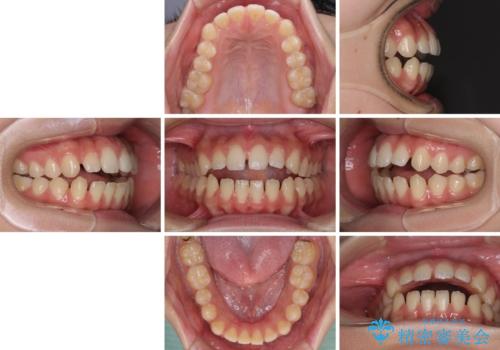

【モニター】隙間だらけの前歯を治したい インビザラインによる矯正治療

- 上下前歯の隙間と咬み合わない前歯を気にして来院された患者様です。

開咬の治療は、前歯を閉じるように動かすとともに、上下臼歯を圧下(骨内にめり込ませる)させることで進めて行きます。

インビザラインは臼歯の圧下を効果的に行えるため、インビザラインを用いて矯正治療を行うこととしました。

開咬とすきっ歯は、舌の突出癖改善が必須となるため、トレーニングを徹底的に行うよう指示しました。